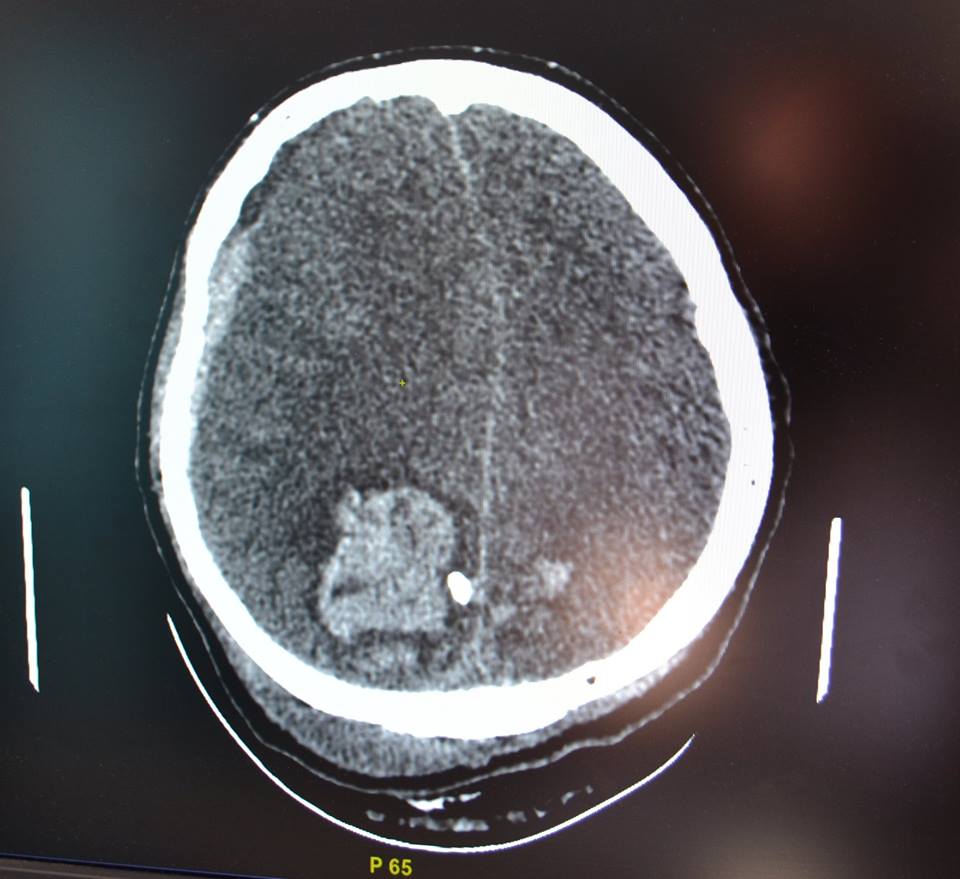

У него тяжелейшее осколочное ранение головы.

Мина взорвалась в трех метрах от них.

Отец перенес множество операций в Мечникова.

Сегодня ночью все лучшие реаниматологи во главе с Игорь Йовенкочетыре раза запускали его сердце.Еще один Герой стал жертвой, защищая будущее Украины и своей семьи.